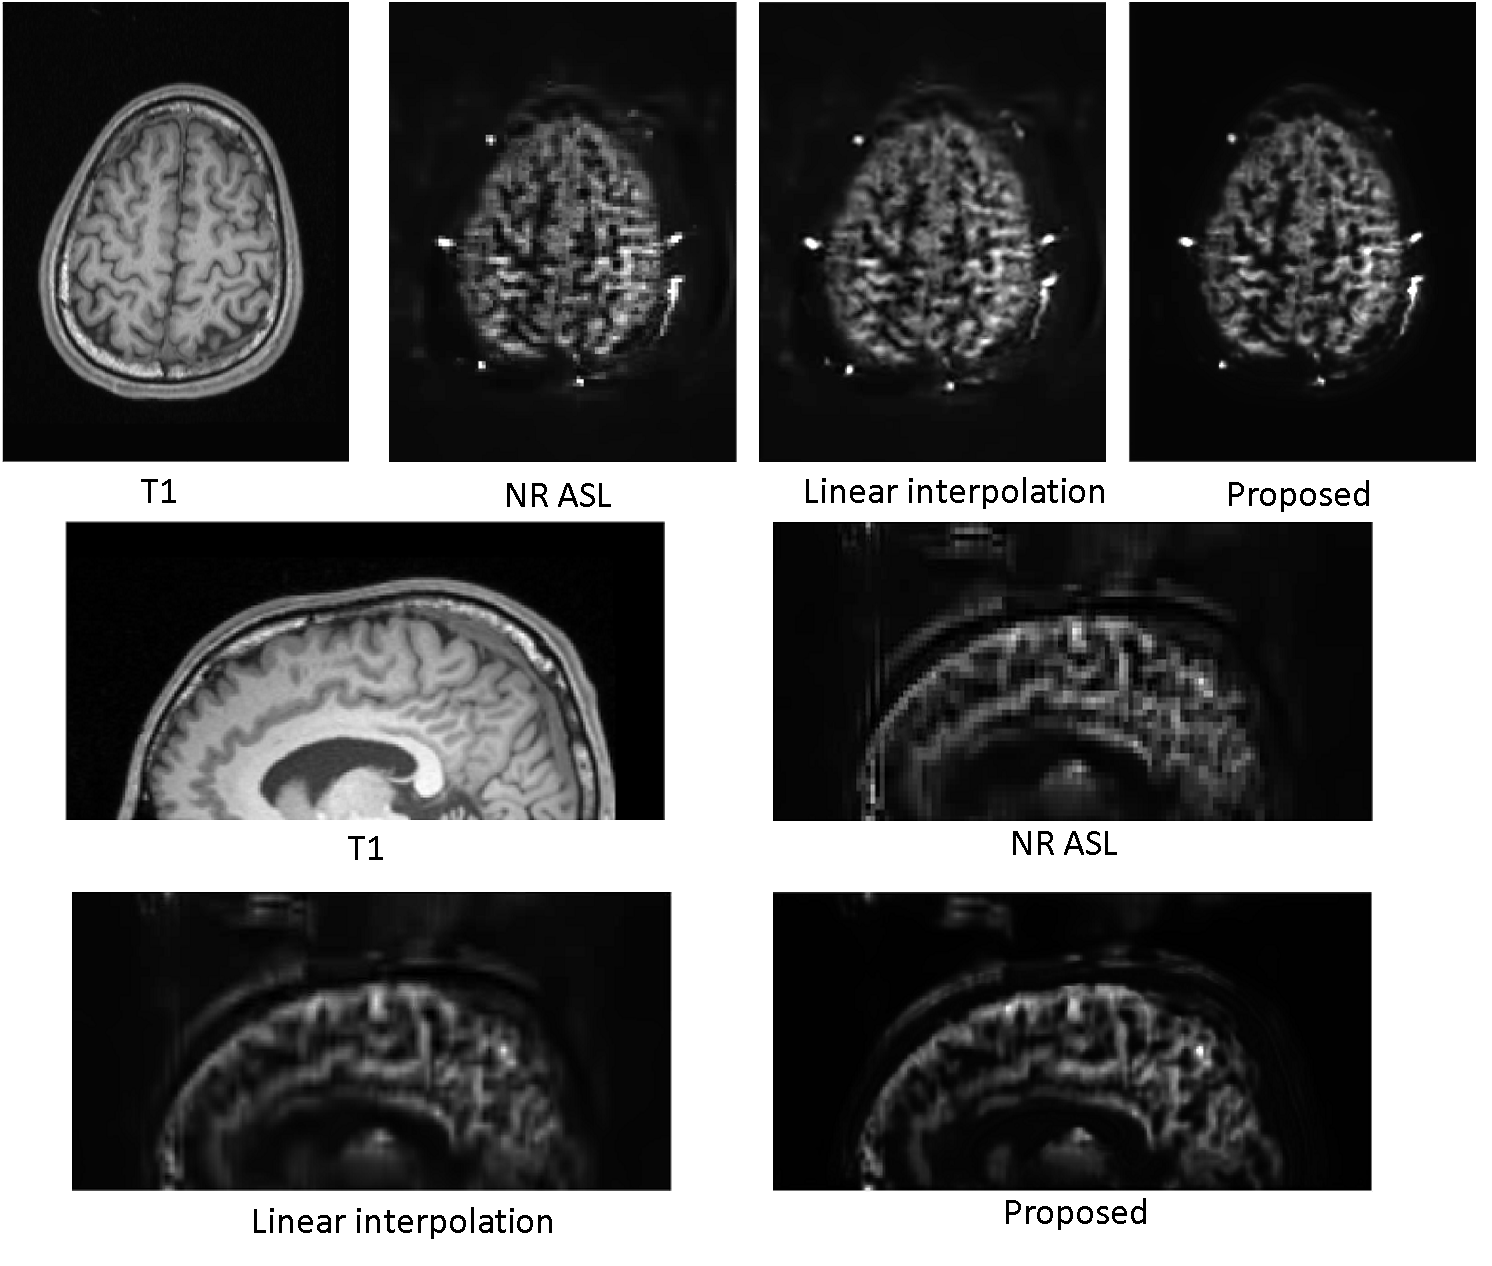

For the second experiment, we trained the network by using the NR ASL image as the training label (Fig. 4), and then generated SR ASL image with the same voxel size () as the T1-weighted image. Successful super-resolution generation of this experiment can prove that this proposed framework can be applied to any existing ASL protocols by translating the voxel size and resolution to that of the T1-weighted image. There is no limit on the voxel-size ratio between the original ASL and the T1-weighted image, which is quite flexible. The results in transaxial view and sagital view shown in Fig. 4 demonstrates this point. The linear interpolation result was chosen for comparison as it has higher PSNR and SSIM than the nearest and spline interpolation in the quantification. The structure of the proposed result is sharp and clear while the linear interpolation result is a little bit blurred.